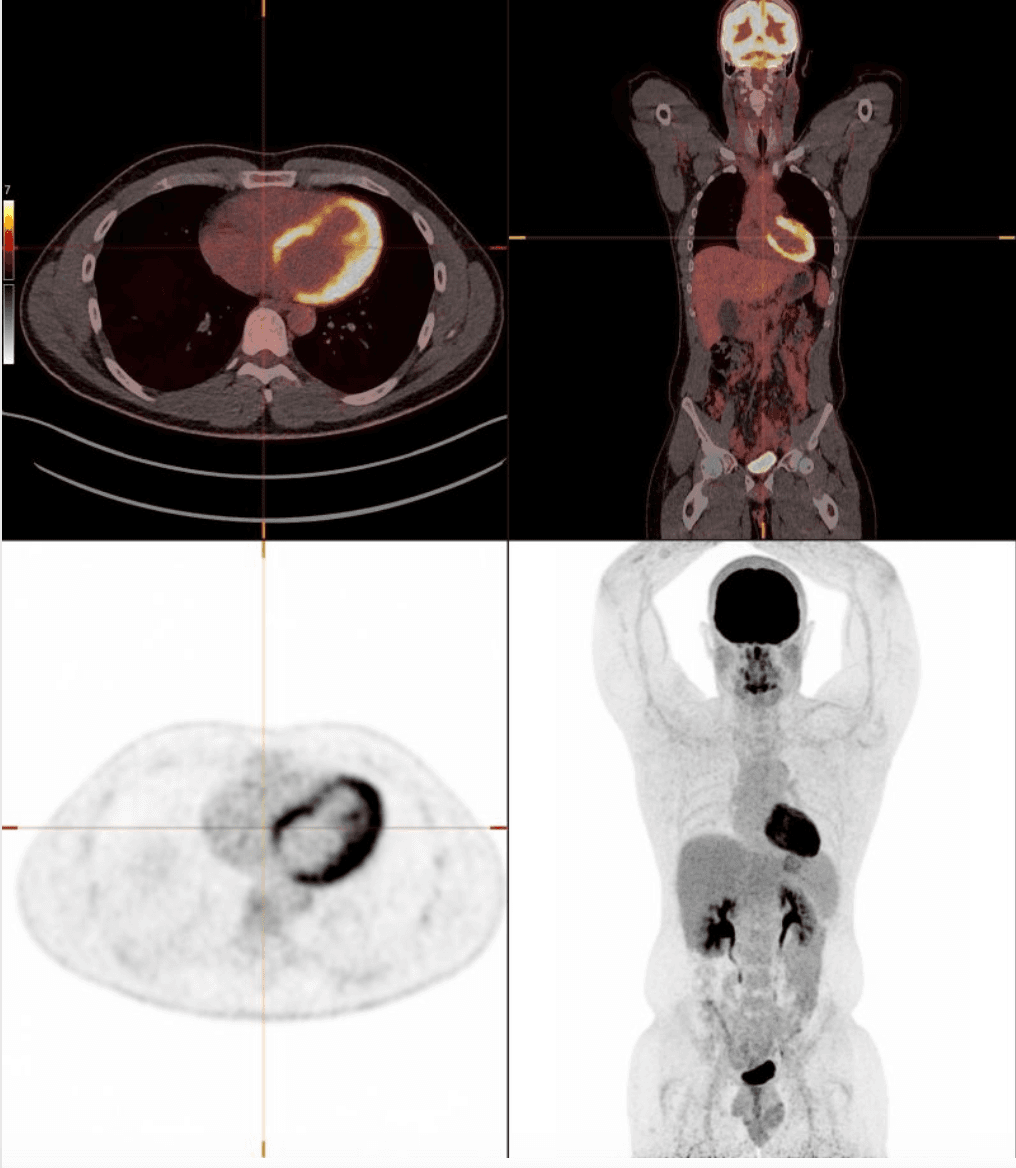

As a nuclear radiologist, I see the endpoint of disease on PET-CT every day. Over time, I kept noticing an early warning sign across ultrasound, CT and MRI: fatty liver disease — a marker of metabolic dysfunction.

Nuclear radiology — precision imaging in a broad array of diseases.

Nuclear medicine and radiological imaging, with a focus on metabolic, inflammatory, cardiovascular and oncological diseases.